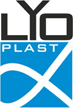

- Дентальную компьютерную томографию проводили на аппарате «Kodak 9000D» до операции цистэктомии с одномоментной резекцией верхушки корня зуба; непосредственно после операции; через 3 и 6 месяцев после цистэктомии.

- Режим томографии: напряжение на трубке составляет 60-90 кВт, анодный ток от 2 до 15 мА, частота генератора 140 кГц, фокальное пятно 0,5 мм CEI, общая фильтрация 2,5 мм Al.

- Размер сканируемой области (цилиндр) – 50×37 мм, размер трехмерного элемента изображения (изотропный воксел) 0,76×0,76×0,76 мм.

- Доза облучения пациента при одном исследовании составляет 0,04 мЗв (время сканирования 40-45 секунд).

- Проводилось построение серии аксиальных и апроксимальных срезов в области дефекта костной ткани.

- Динамика плотности костной ткани и оценка ее структуры с помощью гистограмм проводилась с использованием пакета прикладных программ для обработки медицинских изображений «Medical Imaging Interaction Toolkit» (MITK 2015.05) [11].

- На всех сроках наблюдения оценивали плотность костной ткани в единицах шкалы Хаунсфильда (HU) в зоне дефекта (HUд).

- Для индивидуальной оценки остеоинтеграции определяли плотность костной ткани в реперной зоне интереса (HUр), которую выбирали в прилежащем к дефекту участке здоровой костной ткани, и расчитывали относительную величину - соотношение HUд/HUp.

Компьютерная томография установила значительные различия в рентгеновской плотности остеопластических материалов «CrossBone»® и «Лиопласт»®.

Деминерализованная спонгиоза «Лиопласт»® является рентгенонегативной. Плотность материала, измеренная в первый день после операции РВК (209,08±25,1) оказалась намного меньше плотности здоровой костной ткани (391,25±28,83).

Это объясняется полной декальцинацией этого материала в процессе изготовления и отсутствием в нем минеральных компонентов (рис. 1).

Плотность «CrossBone»® выше плотности костной ткани.

Соотношение плотности зоны дефекта и реперной области (HUд/HUр) на первый день было равно 1,2±0,11.

Высокая плотность «CrossBone»® обусловлена наличием в его составе только неорганических компонентов (рис. 2).

Компьютерные томограммы 22 пациентов I группы показали замещение костного дефекта регенерата через 3 месяца после операции: определяется формирующийся трабекулярный рисунок границы костной полости не дифференцируются от окружающих тканей.

Образование новой костной ткани подтверждено результатами измерения плотности костной ткани.

При использовании деминерализованной спонгиозы «Лиопласт»® через 3 месяца уровень поглощения (HU) костной ткани, формирующейся в области дефекта приближается по своему к плотности реперной зоны.

Средний прирост плотности костной ткани у пациентов I группы составил 86% (табл. 1).

Образование новой костной ткани доказывает соотношение плотности операционной области к здоровой костной ткани, которое в первый день после РВК составляло 0,53±0,04. , а к концу третьего месяца его значение увеличилось практически в 2 раза и приблизилось к единице (рис.3).

Через 6 месяцев все показатели оставались неизменными.

На КТ у 21 пациента II группы на всех сроках наблюдения отчетливо видны гранулы материала, которые не были подвержены резорбции.

Показатели плотности операционной зоны через 3 и 6 месяцев после РВК при применении материала «CrossBone»® схожи с первым днем после операции (рис.3).

Отношение плотности в операционной области к здоровой костной ткани (HUд/HUp) также остается выше 1,0 (табл. 1).